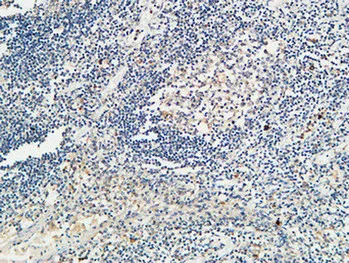

CD68 Rabbit Polyclonal Antibody

Cat: APRab08436